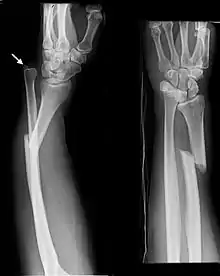

| Monteggia Fracture (type of ulna fracture) | |

Fractures of the ulna can occur at different levels of the bone: near the wrist, in the middle or near the elbow.[2] The fracture may be confined to the ulna or accompanied with damage to the radius or the wrist or elbow joints.[2]

- Monteggia fracture - a fracture of the near to elbow end of the ulna with the dislocation of the head of the radius at the elbow joint.[2]

Monteggia Fracture (fracture of proximal ulna)